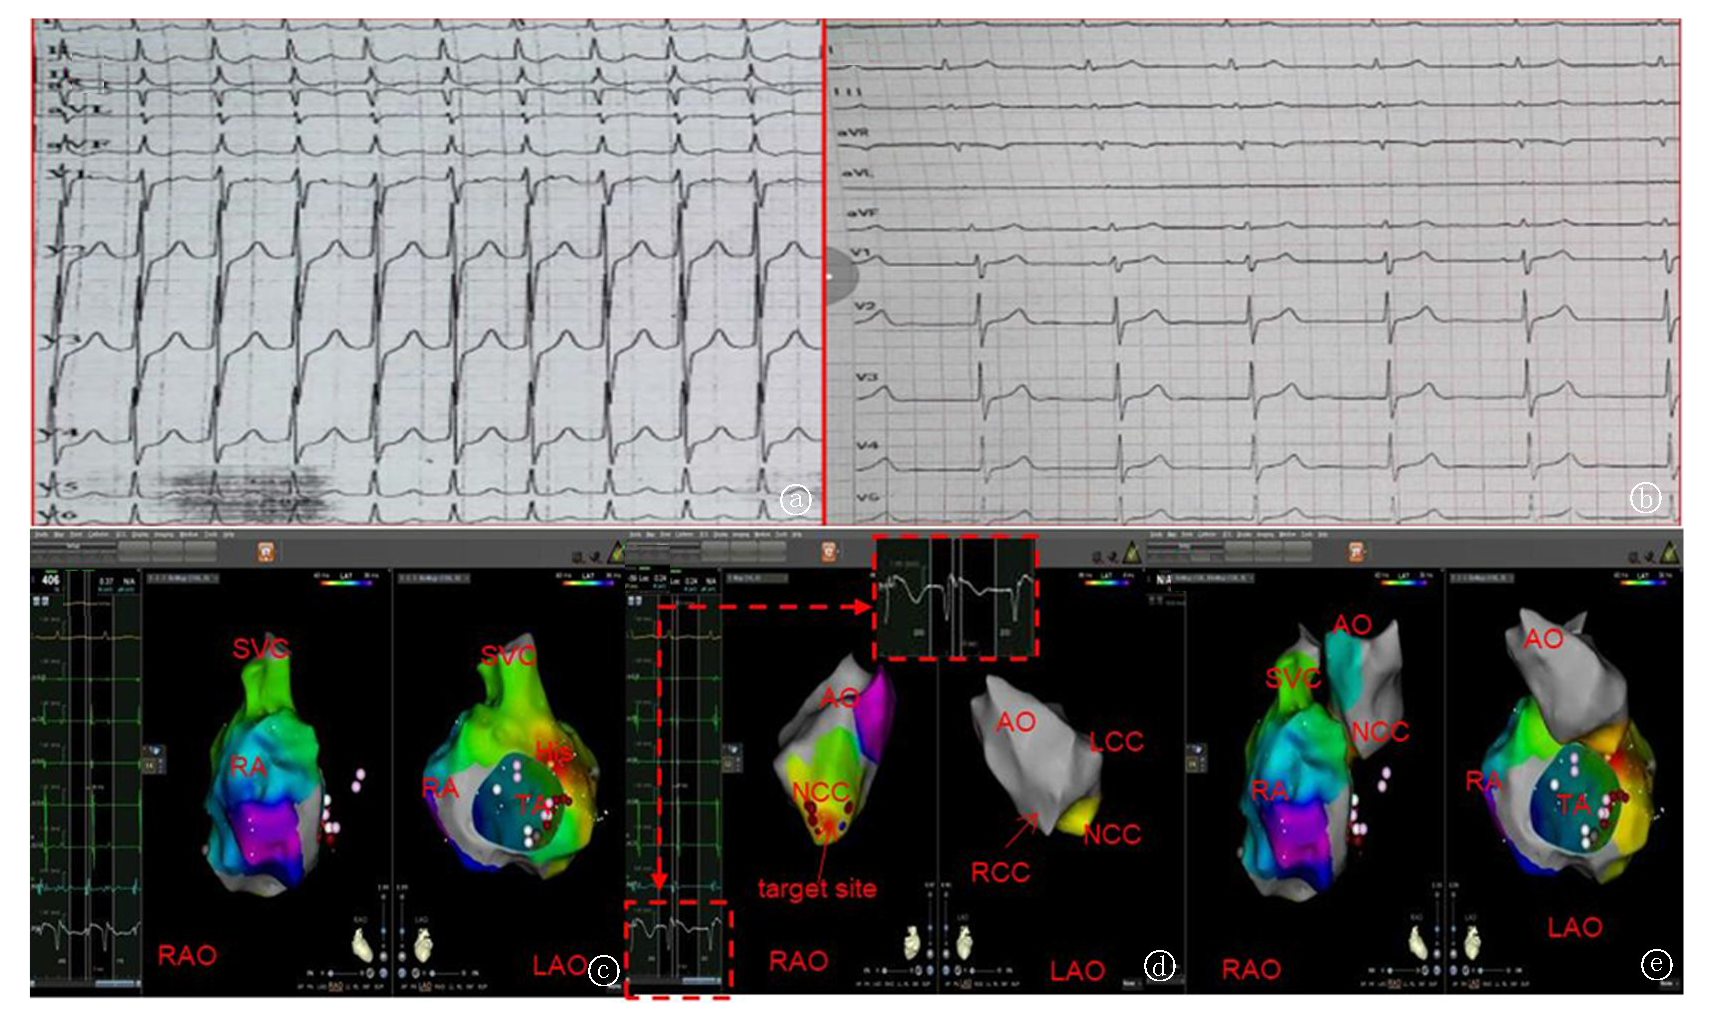

Fig.1 Successful ablation of premature atrial contractions originating near the His bundle region in the NCC a. Preoperative electrocardiogram: P waves are mostly negative/positive biphasic in lead V1 and inferior leads; upright in lead aVR; variable in lead I: low and flat, positive in lead aVL; b. Postoperative electrocardiogram; c. Right atrial mapping, left side is LL (left lateral), right side is LAO (left anterior oblique), yellow points indicate the His bundle, red point shows the earliest activation preceding the surface P wave by 56 ms; d. Fusion image of the aortic sinus and RA:Left side is LL, right side is LAO, yellow points indicate the His bundle, red points indicate the NCC (non-coronary cusp).Note: LL: left lateral

Fig.2 Successful ablation of atrial tachycardias originating near the His bundle region in the NCC a. ECG during atrial tachycardia: P waves appear negative or positive biphasic in lead V1 and inferior leads; upright in lead aVR; negative or positive in lead I, positive in lead aVL; b. ECG after ablation; c. Right atrial (RA) mapping: Left side is RAO (right anterior oblique), right side is LAO (left anterior oblique). Yellow points indicate the His bundle. Mapping near the His bundle septum showed an A wave preceding the surface P wave by 34 ms, but ablation did not terminate the atrial tachycardia; d. Aortic sinus mapping: Left side is RAO, right side is LAO. During atrial tachycardia, mapping showed the earliest local activation at the NCC (non-coronary cusp), preceding the surface P wave by 47 ms, and ablation was successful; e. Fusion image of the RA and aortic sinus: Left side is RAO, right side is LAO. Yellow points indicate the His bundle, red points indicate the earliest activation preceding the surface P wave at the NCC. Note: LCC: Left coronary cusp; RCC: Right coronary cusp; TA: Tricuspid annulus; AO: Aorta